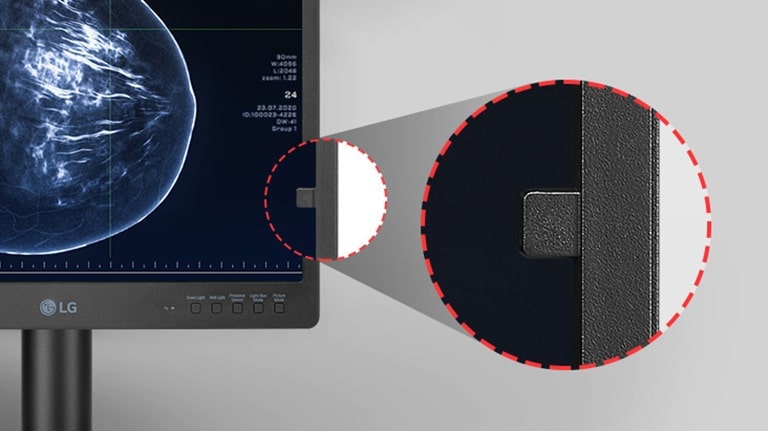

Internal front calibration sensor

Consistency in medical images

The front-sensor, supported by calibration software, enables calibration without the need for additional measuring equipment, ensuring stable image quality.

*All images are shown for illustrative purposes only and may vary from the actual product/usage.